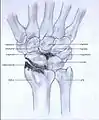

Post-traumatic osteoarthritis can be classified into four stages.[1][6] These stages are similar between SLAC and SNAC wrists. Each stage has a different treatment.

- Stage III: the osteoarthritis is localized in the entire radioscaphoid joint with involvement of the capitolunate joint.

Stage III